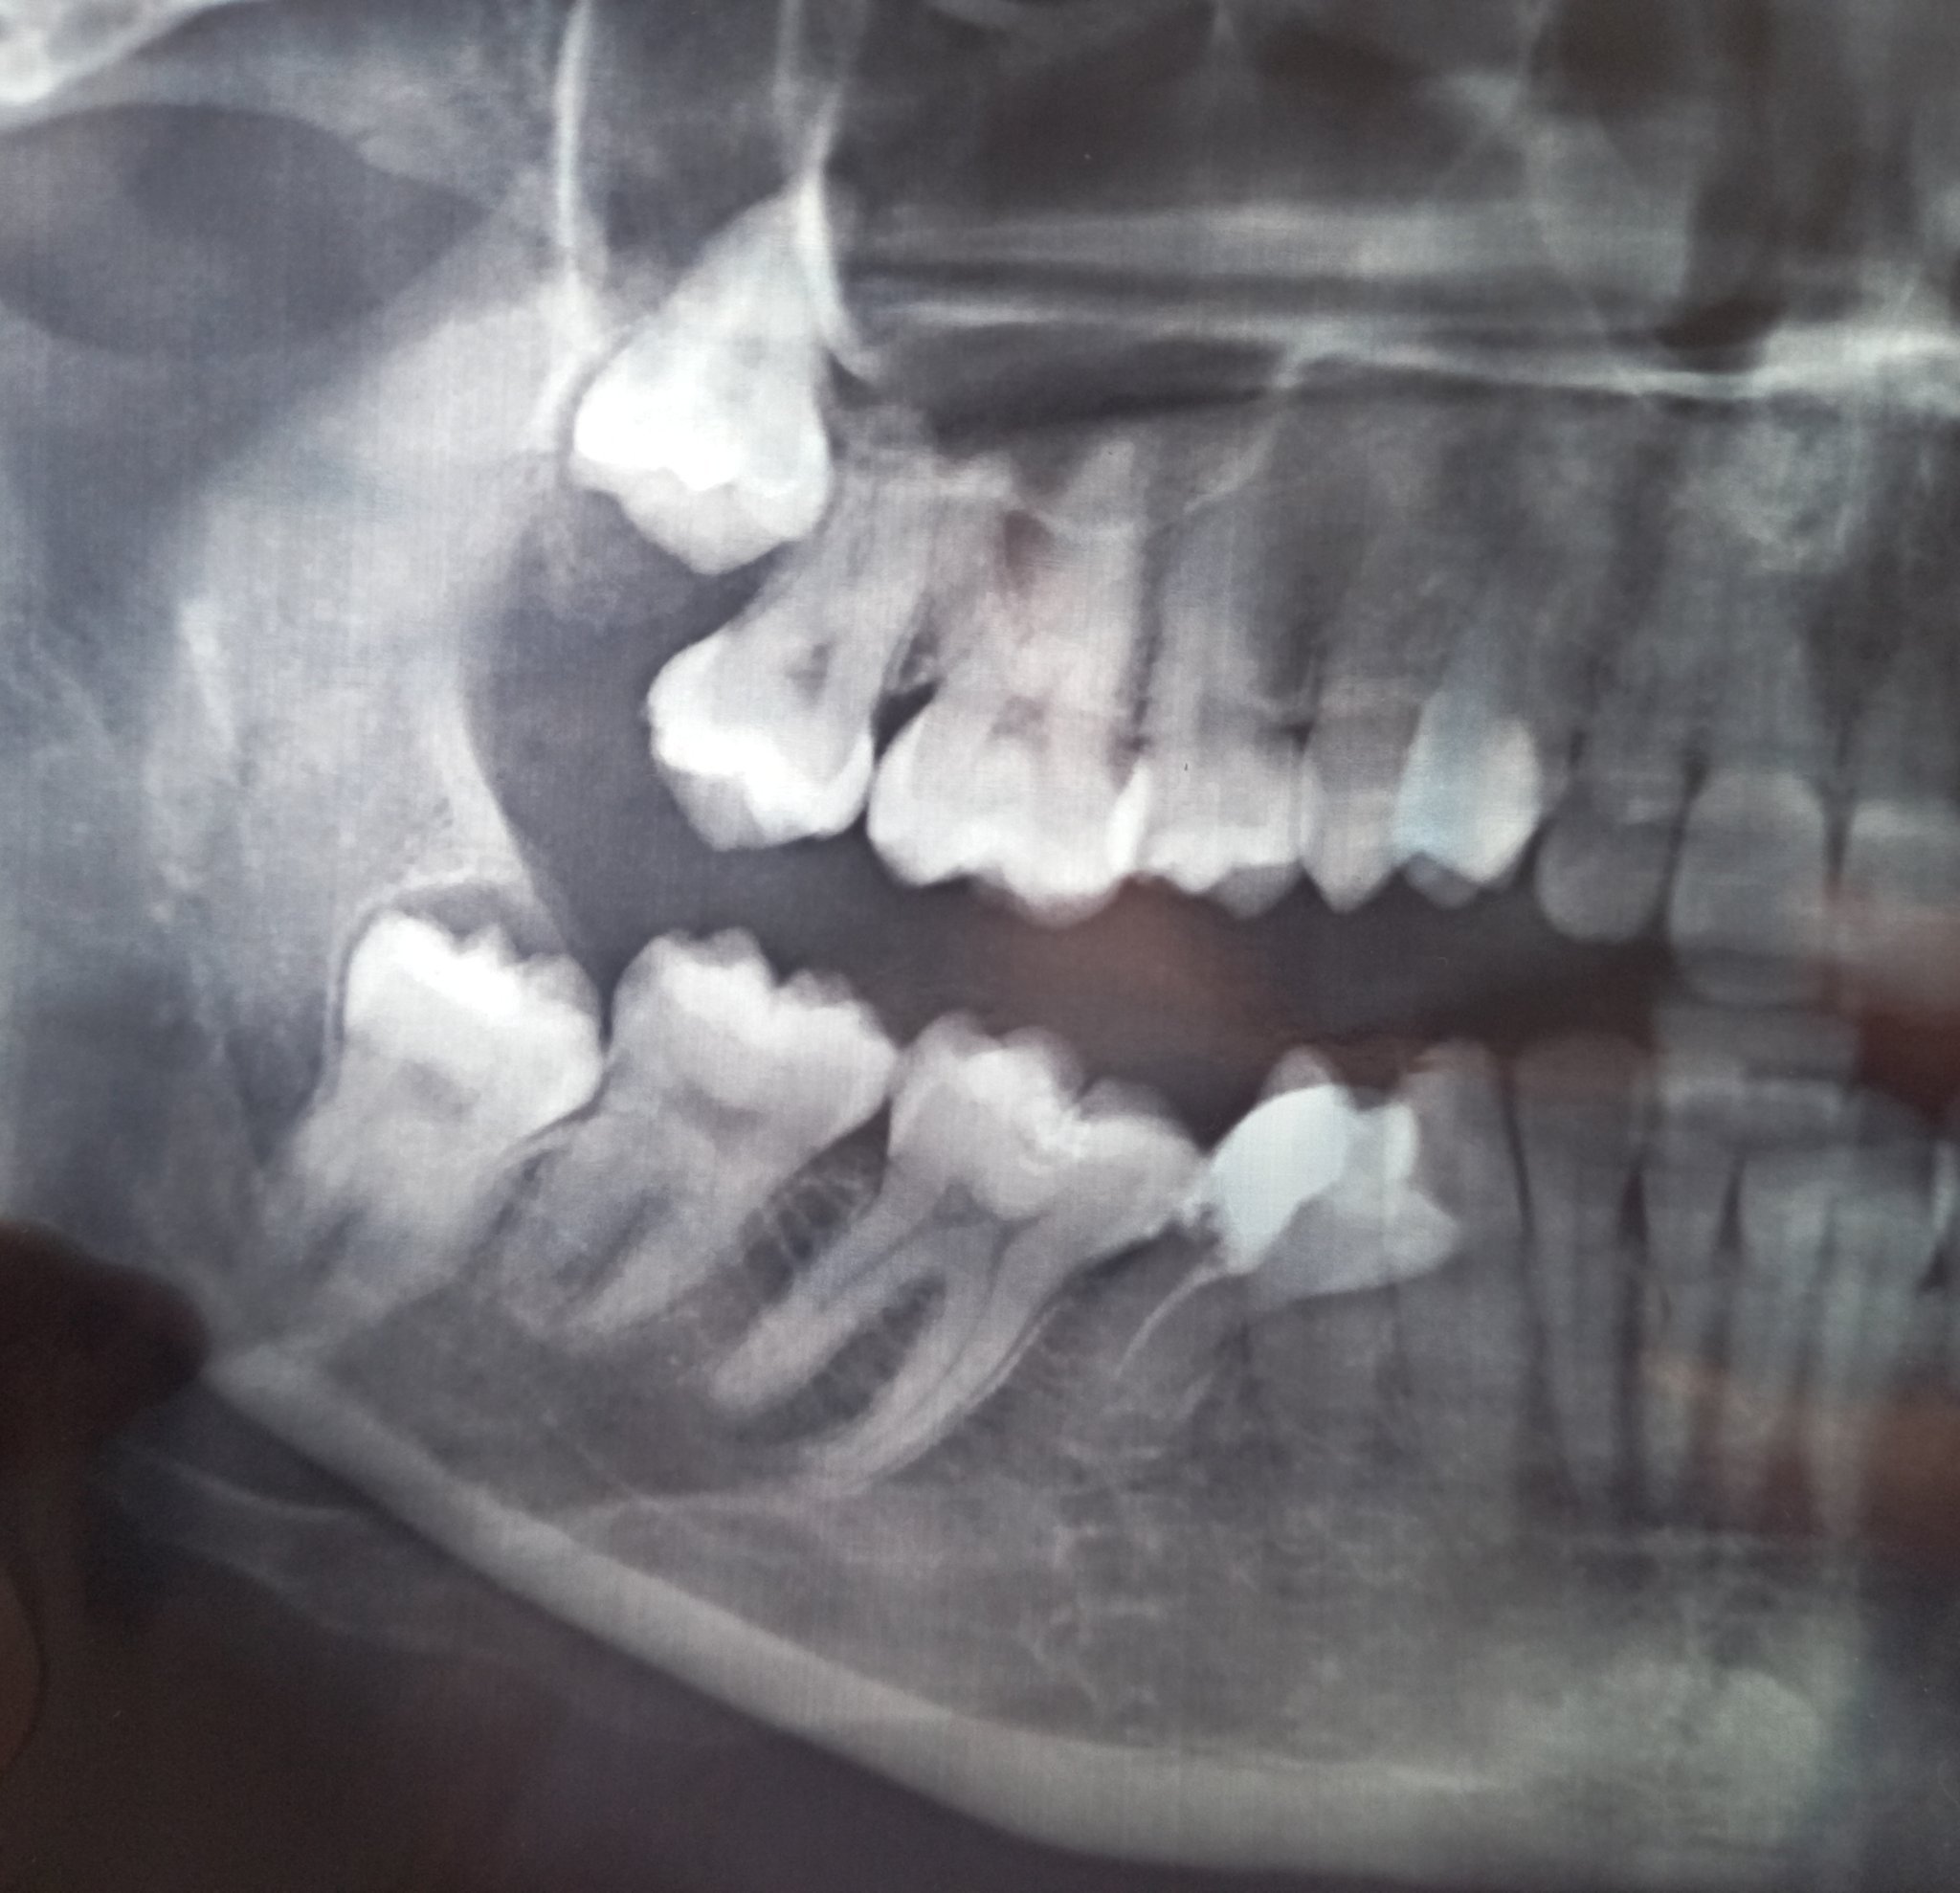

Здравейте д-р Маринов, имам сложен проблем, след недобро кореново лечение и поправки от неизчистен кариес(5ти ляв долен зъб,беше и леко крив ) получих пулсации около зъбите от 4ти наляво чак до венеца.Има миризма на гной, на снимка не излиза от къде е локализирана гнойта.Премахнаха ми зъба, но състоянието продължава.Пулсации без болка и миризма на гной от някъде в края.Може ли да каже на какво се дължи и как да се открие проблема?Имам отпадналост и сърцебиене, безапетитие от тогава.Възможно ли е около костта или в лигавицата на венеца да гнои или пък под съседни зъби да е преминало възпалението?Правихме дренаж и на венеца над мъдреца, не излиза нищо в дренаж.